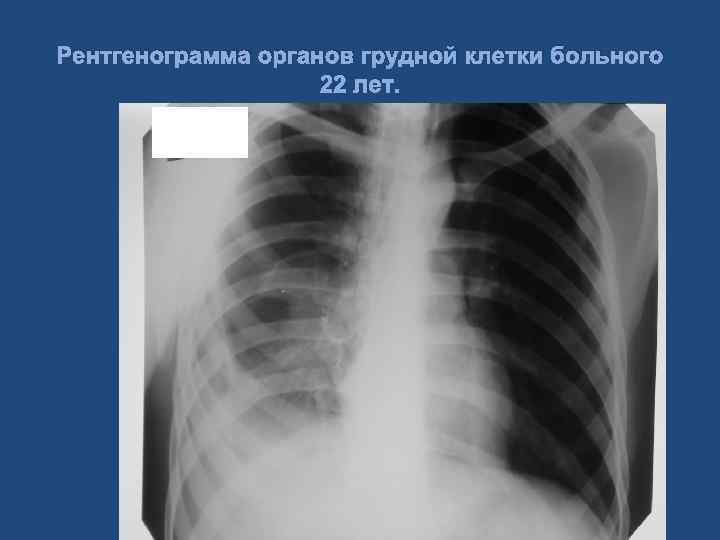

Клиническое наблюдение. Больной 22 лет. Диагноз: Тяжелая сочетанная травма. Тупая травма грудной клетки, двусторонний посттравматический гемопневмоторакс. Тупая травма живота, множественные разрывы правой доли печени, гемоперитонеум. Геморрагический шок Ш ст. 63

Клинический пример больного, 22 года Рентгенограмма органов грудной клетки больного 22 лет, при поступлении.